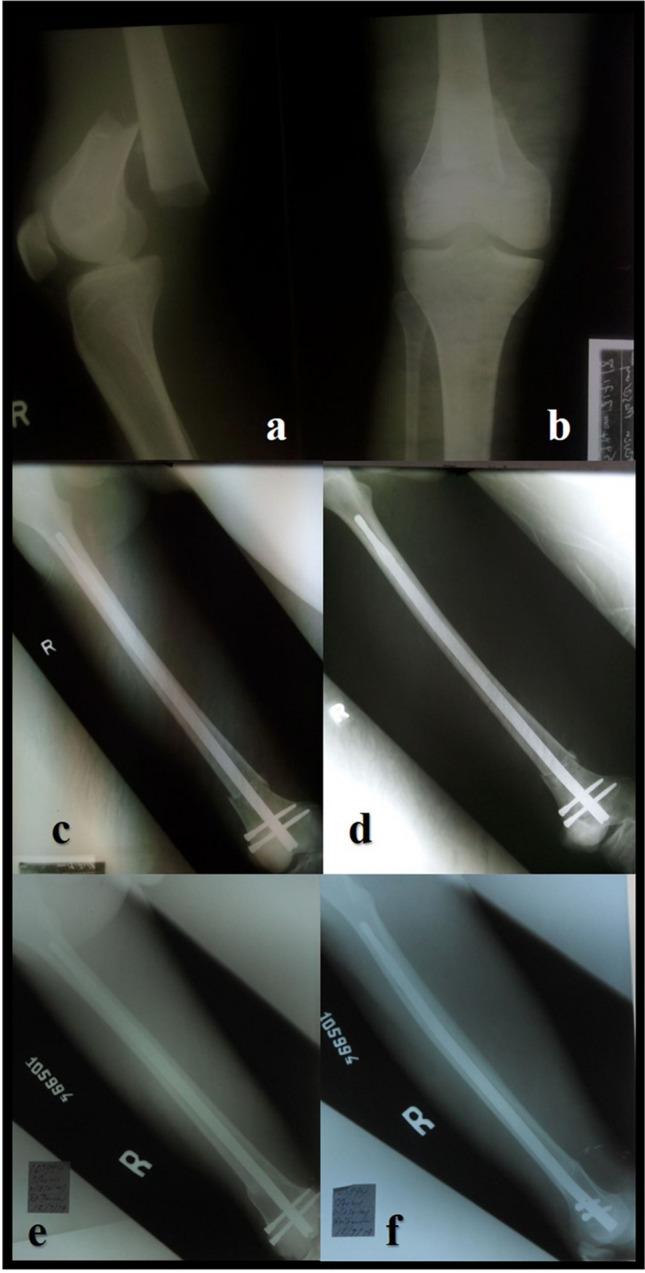

Femoral fractures are common in low and middle-income countries (LMIC), predominantly caused by high-energy trauma. The surgical implant generation network (SIGN®) program offers two different intramedullary nails in LMIC which are designed to be used without image intensifier free of charge for the patients: the SIGN standard nail (SSN®) and the SIGN Fin nail (SFN®). This study aimed to compare the results of the SSN® and the SFN® for the treatment of middle and distal shaft femoral fractures through a retrograde approach.

This was a retrospective, descriptive, and non-experimental study including all consecutive patients who underwent surgical management of middle or distal shaft femoral fracture between January 2017 and May 2022 in an NGO hospital located in Freetown, Sierra Leone. The duration of surgery, type of reduction, complications like screw loosening, implant migration, anterior knee pain and non-union rate at six months of follow up were evaluated.

A total of 122 patients were included in the study. Group A: 60 patients were managed with SSN® and Group B: 62 patients with SFN®. The mean operative time was 104 min with SSN® and 78 with SFN® (p < 0.001). Open reduction of the fracture was necessary in ten (16.7%) patients with SSN® and 12 (19.4%) patients treated with SFN® (p = 0.69). Non-union was observed in one (1.7%) patient with SSN® and two (3.2%) patients with SFN® (p = 0.57).

Both options seem equally effective in treating midshaft and distal femoral shaft fractures. The SFN® reduces the surgical time, due to this fact, in polytraumatized patients, patients with bilateral femur fracture or patients with ipsilateral tibia fracture, it can be considered as the best option to be used. There was no statistical difference in the complications presented by the two groups.